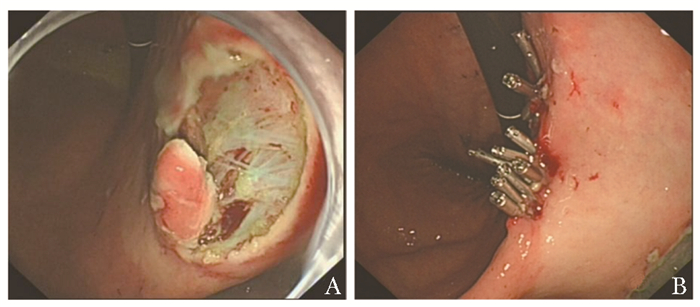

• 摘要: 乳腺癌作为女性恶性肿瘤中最常见的肿瘤之一, 多向骨、肝、肺等部位发生转移, 而乳腺癌胃转移的病例较为少见, 与原发性胃癌的鉴别亦是临床工作中的一大难点。本文报道1例乳腺癌胃转移患者, 根据该患者的免疫组化结果, 结合病史, 最终诊断为起源于乳腺小叶癌的转移性浸润性胃腺癌, 行内镜下黏膜剥离术后给予氟维司群注射液联合阿贝西利内分泌治疗, 患者预后良好。本文总结该患者的临床表现、诊断及治疗经过, 以期为乳腺癌胃转移的临床诊疗提供参考。

Abstract: Breast cancer, one of the most common female malignant tumours, mostly metastasizes to the bone, liver and lung. The case of gastric metastasis of breast cancer is relatively rare, and the differentiation of breast cancer from primary gastric cancer is also a major difficulty in clinical practice. In this paper, we report a rare case of gastric metastasis from breast cancer, which was diagnosed as metastatic invasive gastric adenocarcinoma originating from lobular carcinoma of the breast according to the immunohistochemical results of the patient, combined with the patient's medical history. The patient was given fulvestrant injection combined with abecycline for endocrine therapy against tumour after endoscopic mucosal dissection, and the prognosis was good. The clinical manifestations, diagnosis and treatment of this disease are discussed through relevant literature review, with the aim of providing reference for the clinical diagnosis and treatment of gastric metastasis of breast cancer.